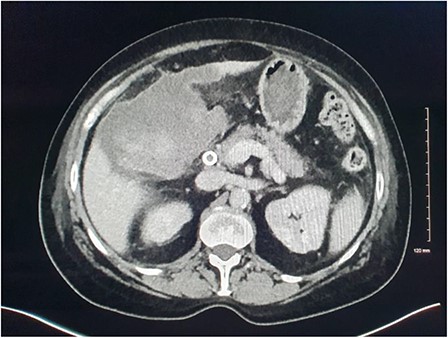

Magnetic resonance imaging (MRI) of the liver and magnetic resonance cholangiopancreatography (MRCP) were performed in the following days, which demonstrated a frank rupture of the gallbladder and a patent biliary tree (Fig. 3). After a few more days, the patient became peritonitic and a further CT was performed. This demonstrated a moderate volume of peritoneal free fluid and haematoma in the gallbladder fossa (Fig. 4). Ultrasound-guided drainage of peritoneal fluid was performed producing bilious fluid. ERCP was performed, which demonstrated ongoing leak from the gallbladder fossa (Fig. 5) and allowed placement of a covered biliary stent to divert flow away from the cystic duct.

CT demonstrating large volume of bilious peritoneal fluid with haematoma and calculus in the gallbladder fossa.